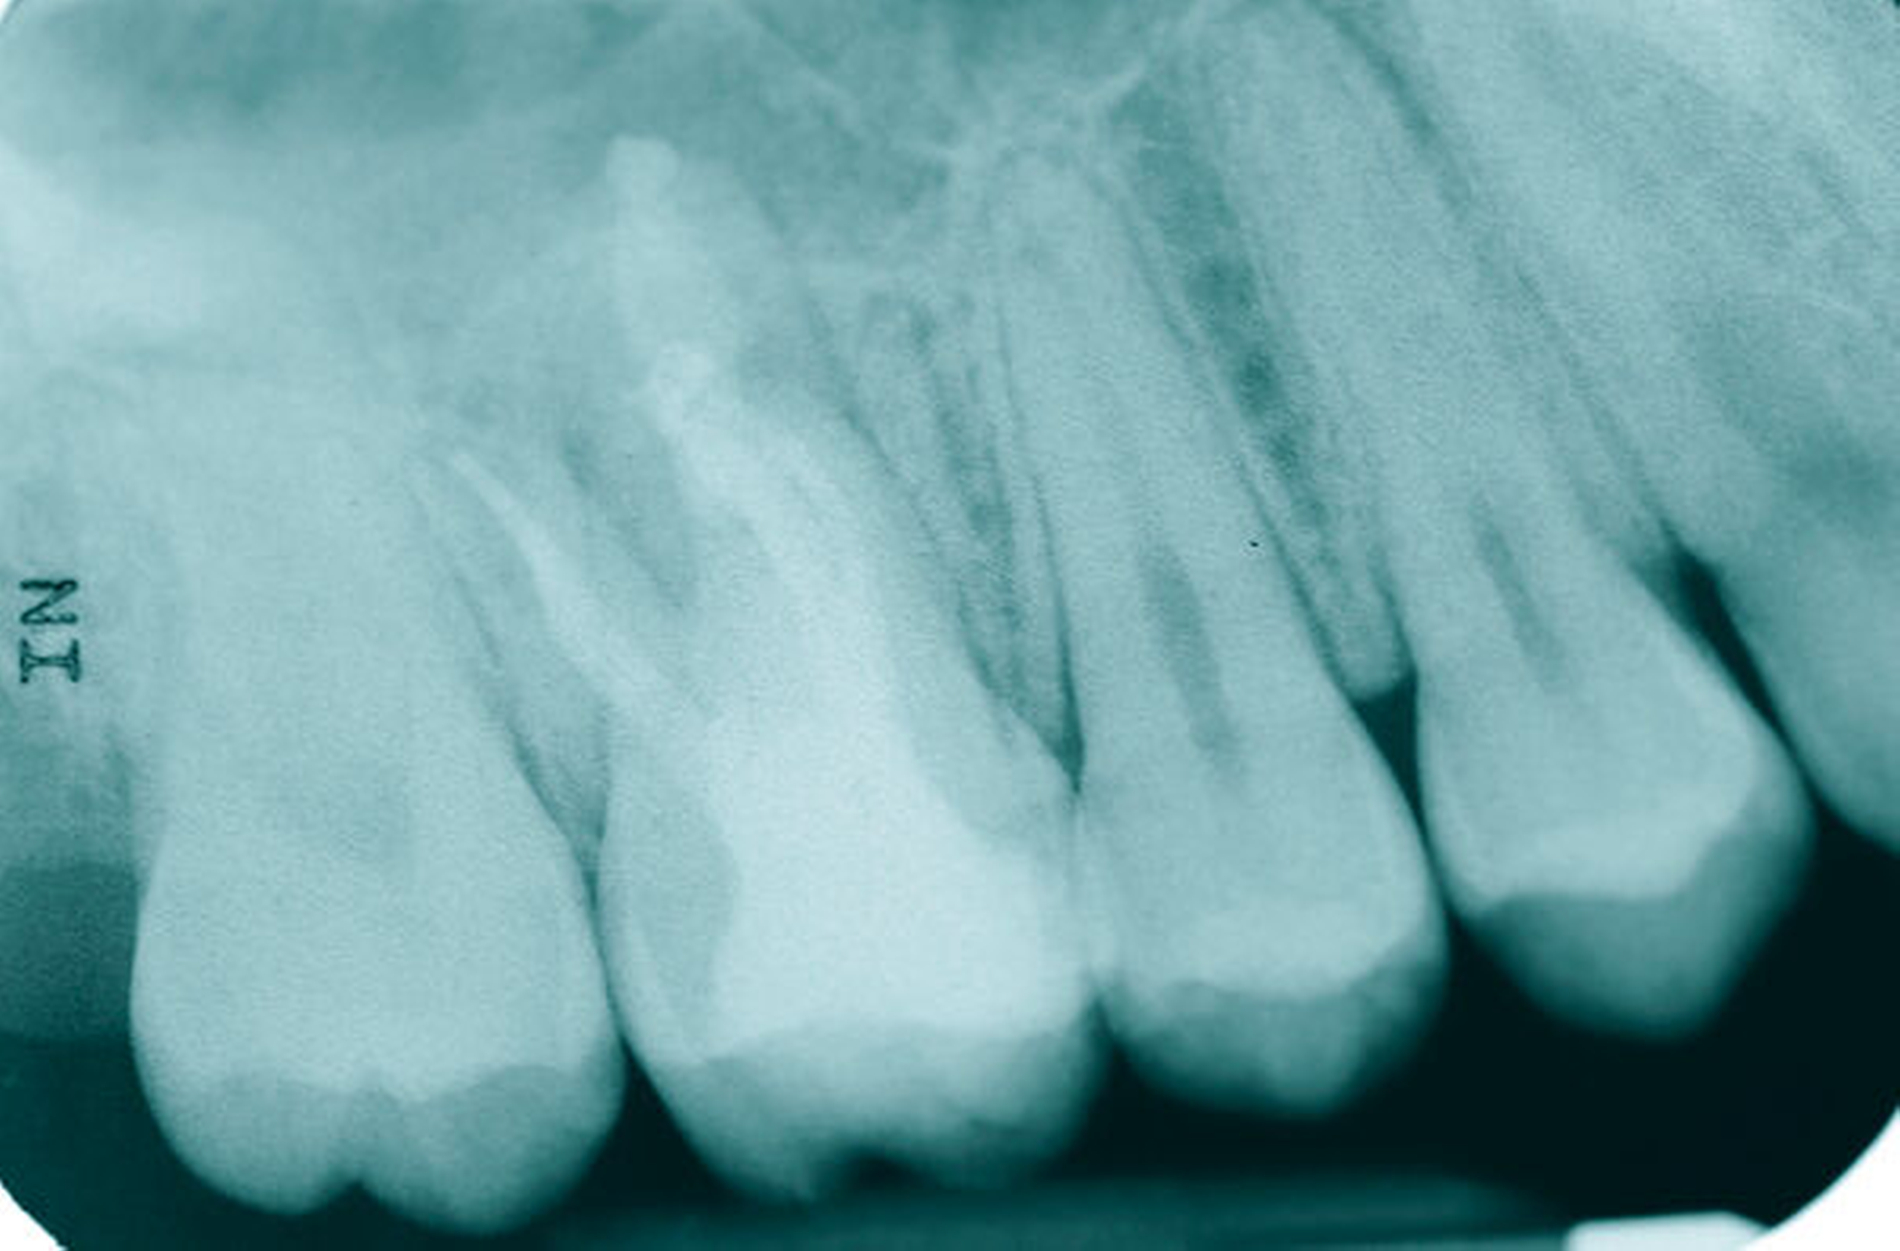

Eine 53-jährige Patientin stellte sich 2015 mit plötzlich aufgetretenen, starken Beschwerden an Zahn 16 und der Bitte um Abklärung vor. Es erfolgte die klinische und röntgenologische Befundung des Zahnes, der neben einer apikalen Parodontitis auch eine große, fast bis in die Furkation reichende Kronenrandkaries an der mesiobukkalen Wurzel aufwies. Um diesen vorhersagbar versorgen zu können, wurde der Patientin die endodontische Behandlung mit Amputation der mesiobukkalen Wurzel und anschließender Versorgung mittels Vollkrone als Alternative zur Extraktion aufgezeigt. Sie entschied sich für den Zahnerhalt.

So folgte nach der Wurzelfüllung die Amputation der mesiobukkalen Wurzel. Der Zahn wurde nach der Amputation auf Wunsch der Patientin zunächst mit einem Langzeitprovisorium versorgt, das im Verlauf gegen eine definitive Versorgung ausgewechselt wurde. Die Patientin ist seitdem an 16 beschwerdefrei, der Zahn ist stabil und hat eine gute Langzeitprognose.